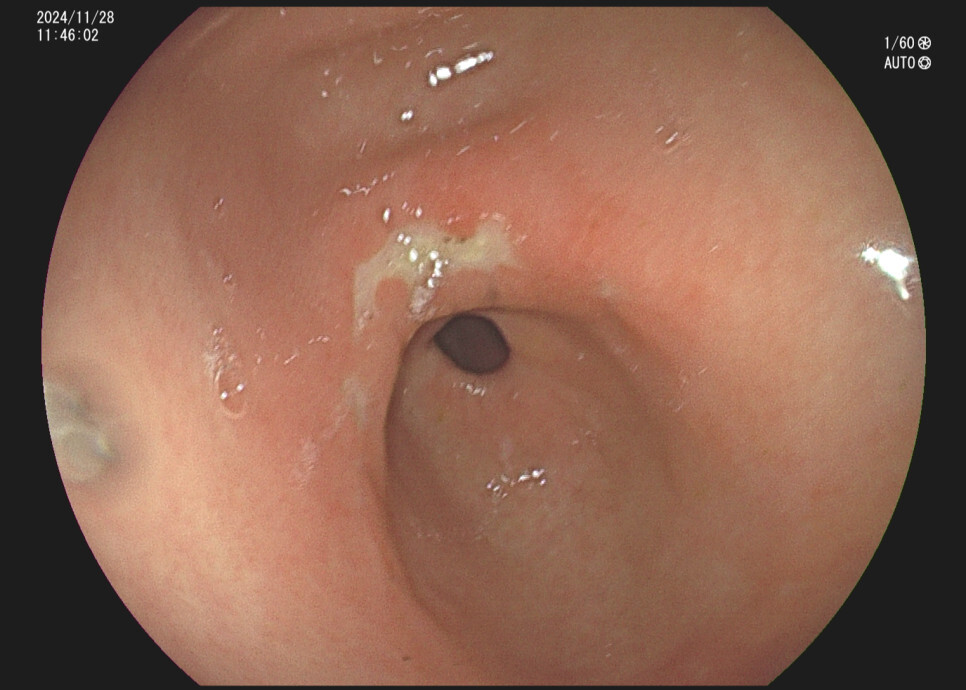

위궤양의 내시경 소견 증례입니다.

사례 3. 35세 여자, 공복의 속쓰림 주소로 내원